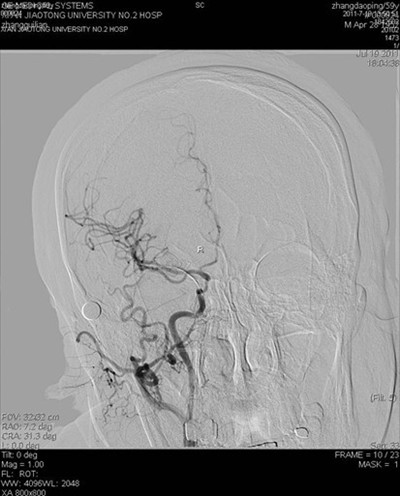

(图2) 闭塞再通血管成形及支架植入后病灶部位显影良好

(图3)术后病灶血管远端颅内血管显影良好

患者张某,59岁,以左侧肢体活动不灵14天入院,14天前患者突然出现左侧肢体无力,活动受限,并言语含糊,曾于外院就诊,脑CT及MR提示脑梗死,治疗后效果不明显,遂来我院。既往有高血压史数年,长期间断服降压药。入院查体:血压180/100mmHg,左侧口角低,左侧鼻唇沟浅,左侧上下肢瘫痪,肌力III+,左侧肢体共济运动差,左侧巴氏征阳性。余查体未见明显异常。辅助检查:空腹血糖9.8mmol/l。根据患者病史、外院影像学检查,考虑诊断为1.脑梗死(分水岭区);2.高血压病(III级,极高危);3.糖尿病(2型)。为了进一步明确患者脑梗死病因,确定下一步治疗方案,在家属签字同意下,于2011年7月19日进行了全脑血管造影术,术中发现右侧颈内动脉开口处闭塞,但远端血流通过后交通依稀可见,经过我科介入小组缜密讨论,拟给患者行闭塞血管再通手术,经过2小时的紧张手术,取得了很好的手术效果,患者安返病房(见图)。本次手术的成功,是继6月我们对急性闭塞血管进行取栓,我院神经介入工作的又一次突破,在血管闭塞后14天再通,在国内外少见报道,这将快速推动神经介入工作的进一步发展。